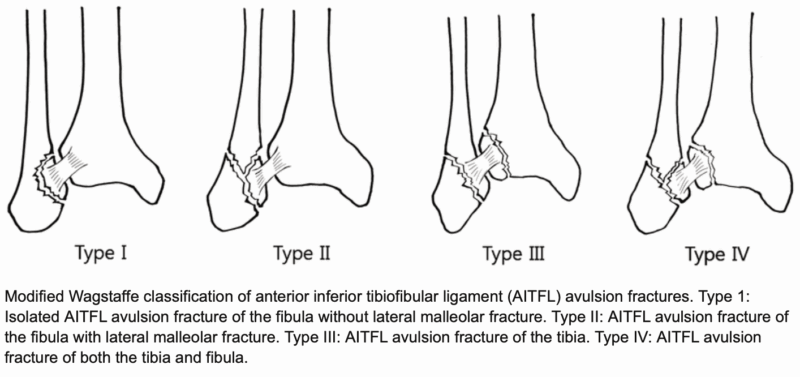

X線写真では骨折はなかったのですが, CTでは外果の前方にヒビが入るように骨折(亀裂骨折)があることが判明しました. Wagstaffe分類では, Type Iでした. 骨折部にズレがないため, ギプス製の板を当てて, 固定しました. 独り暮らしとのことでしたので, 痛みが引くまでの間, 入院するかどうか聞いたところ, 松葉杖を使って帰るとのことでしたので, 理学療法士に松葉杖の使い方を指導してもらった後, 帰宅していただきました. 明日以降, 自宅で過ごせないようならば, 入院可能なので, 連絡をいただくように説明しました. 通院に都合が良い, 後輩医師の整形外科クリニックに紹介しました.